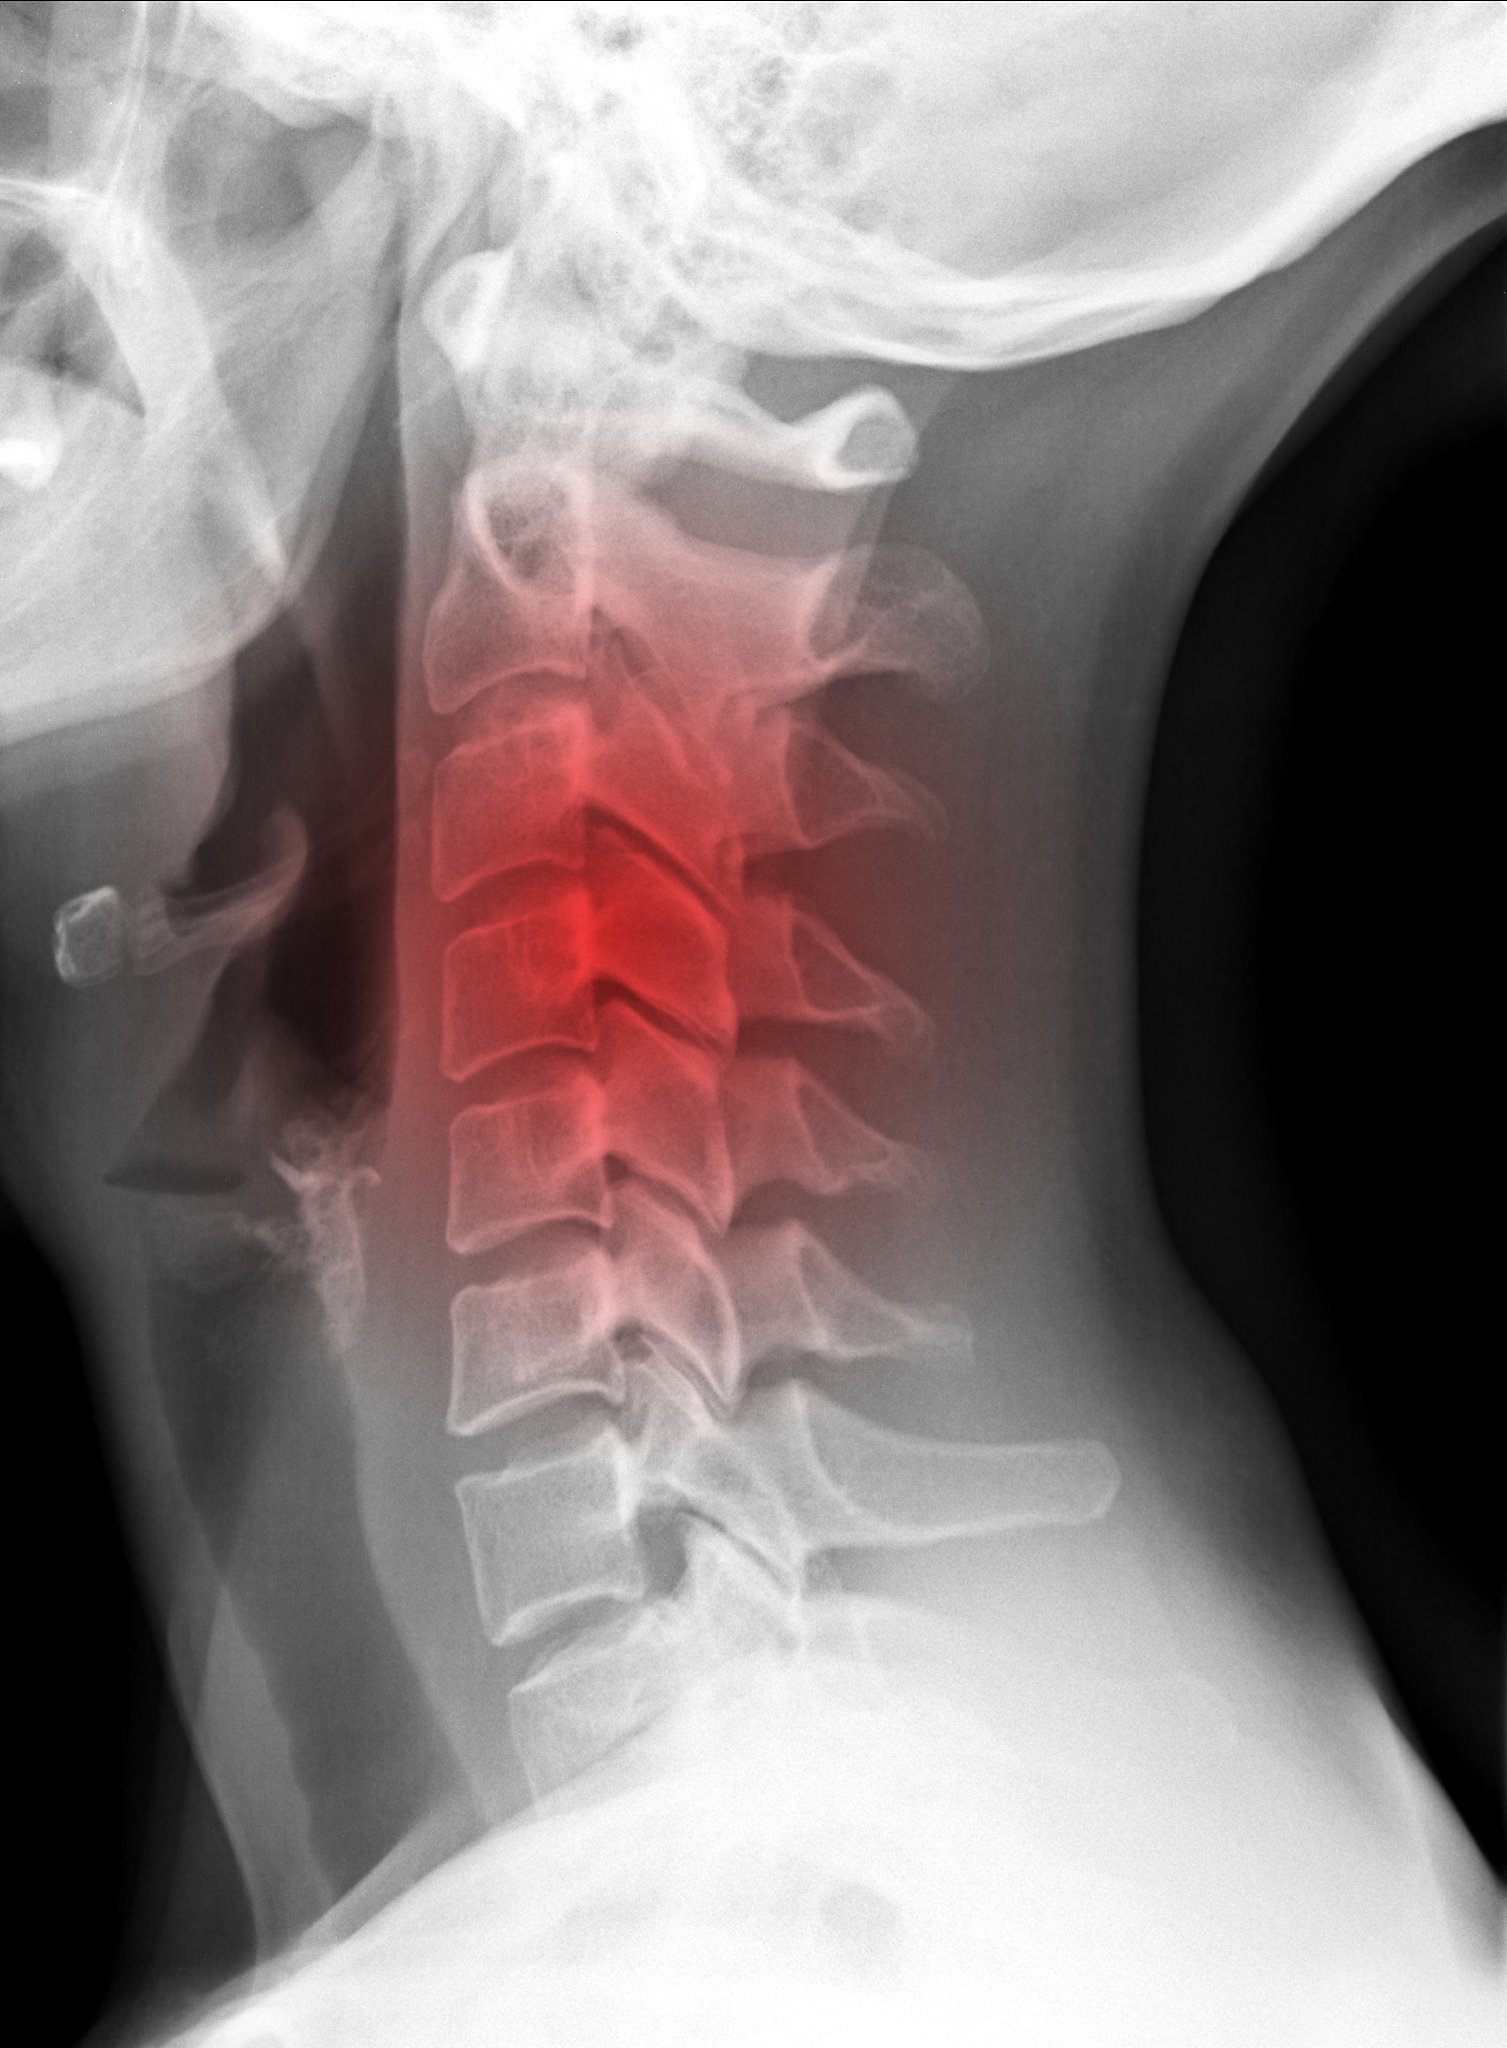

腰椎骨质增生,也称为腰椎退行性变或腰椎骨刺,是一种常见的脊柱退行性病变。它是由于年龄增长、长期过度使用腰椎、损伤或其他疾病引起的椎间盘退行性变,导致椎间盘间隙变窄,骨质增生,形成骨刺等病变。

腰椎骨质增生的症状包括腰痛、腰部僵硬、下肢放射痛、活动受限等。严重的骨刺可能会压迫或刺激脊髓和神经根,导致疼痛、感觉异常、肌力减退等症状。